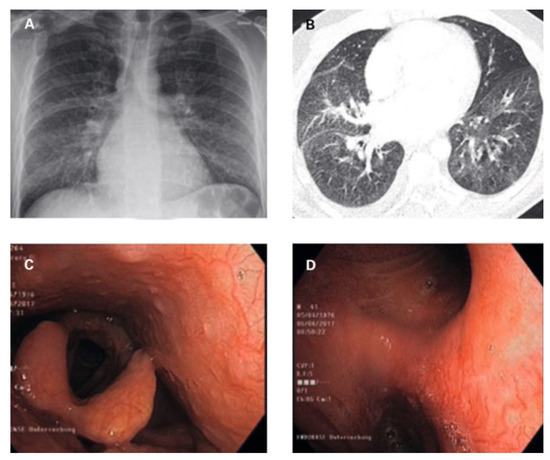

Hemoptysis and Unintentional Weight Loss in a 46-Year Old Patient—Always a Pulmonary Problem?

by Tobias Höfflinghaus, Lena Gerstner, Stephan Wieser and Matthias Meyer

Cardiovasc. Med. 2022, 25(2), 48; https://doi.org/10.4414/cvm.2022.02197 (registering DOI) - 1 Mar 2022

Occasionally, cardiac disease may manifest acutely with extracardiac symptoms. We present a patient case with pulmonary haemorrhage as the first manifestation of rheumatic mitral stenosis, which resolved completely after mitral valve surgery, and discuss the pathophysiology and clinical management of this rare manifestation [...] Read more.

Occasionally, cardiac disease may manifest acutely with extracardiac symptoms. We present a patient case with pulmonary haemorrhage as the first manifestation of rheumatic mitral stenosis, which resolved completely after mitral valve surgery, and discuss the pathophysiology and clinical management of this rare manifestation of rheumatic heart disease. Full article

Figure 1